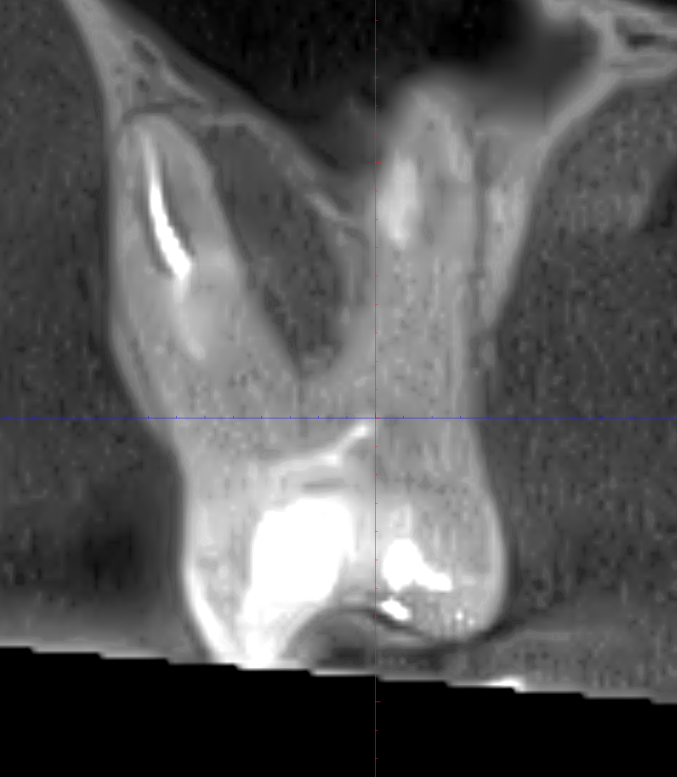

Здраствуйте. Сделал КТ снимок верхней челюсти. Врач дал такое описание проблемного 16 зуба, в области которого есть воспаление: "не исключается линейный перелом или смещение дистального корня зуба 16. вдоль дистального щечного корня с небной стороны так же определяется расширение перидонтальной связки".

Здравствуйте! По снимку, который предоставлен, виден воспалительный хронический процесс, пломбировочный материал в корневых каналах. Увидеть трещину/перелом можно либо в определенной проекции на снимке, либо при диагностическом препарировании зуба под микроскопом(убрать пломбу, удалить из корневых каналов пломбировочный материал, просушить зуб и посмотреть). Если трещина диагностируется- это точно удаление. Если трещины не будет, то зуб будет рекомендовано удалить, но будет возможность переличить. То есть любой зуб с воспалительным процессом рекомендован к удалению. Далее возможны варианты.